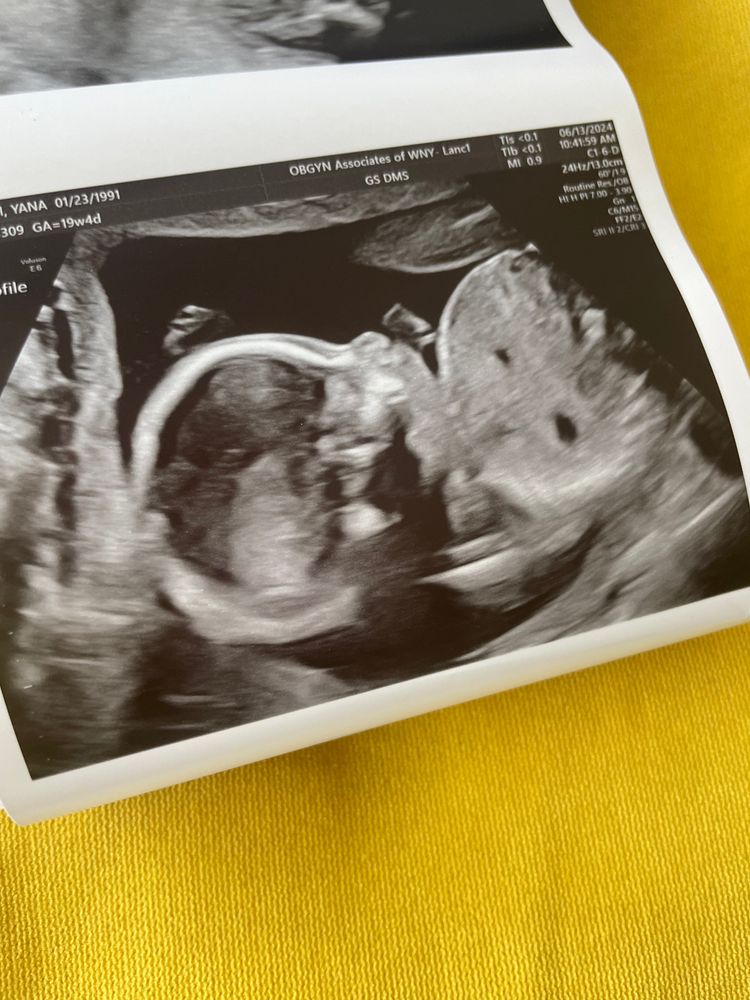

2й скрининг, отстрелялись

Анализы, скринингиПрошли второй скрининг, вроде, все ок.

В США не разрешено комментировать узи, но я видела, что у нее не было вопросов.

меня должны снова проверить 11 июля из-за плаценты, сказали, что она лежит низковато. Норма - от 2 см, у меня 1.75см, что не критично, никаких ограничений нет, просто нужно еще одно узи.

малыш весит 311 грамм и вместо 19н4д измеряется в 20н2д, но она сказала, что это из-за длинных ног😂